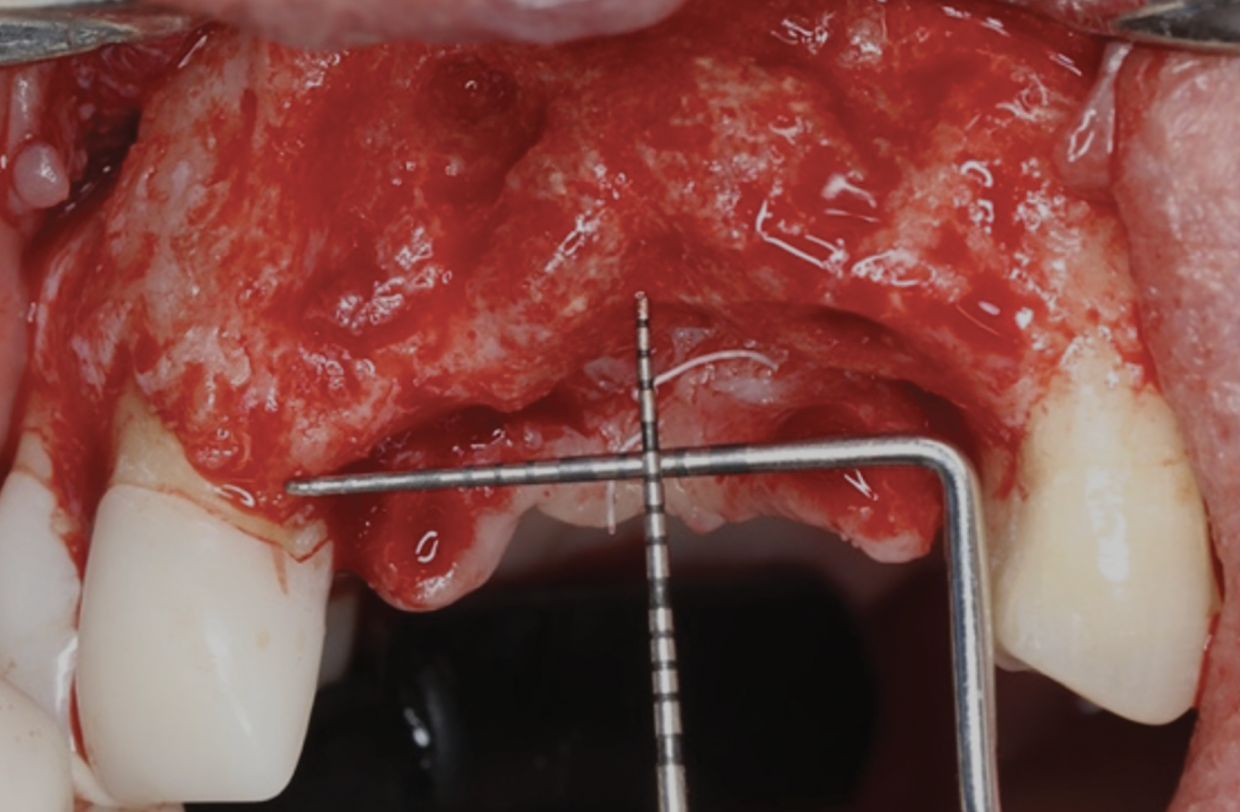

This approach was effective in increasing the horizontal and vertical soft-tissue thickness around the three implants. Nevertheless, a distortion of the MGJ was still present (Figure 13). Therefore, 3 months after the iCTG augmentation, it was decided to perform a second soft-tissue augmentation procedure with the goal of repositioning the MGJ in an adequate level on the buccal aspect, increasing the width of the keratinized mucosa at the implant sites. A modified apically positioned flap was performed (Figure 14). Two labial strip gingival grafts were harvested from the anterior mandible and maxilla and sutured onto the recipient bed with a 7-0 polyglycolic acid resorbable suture.5,17,18 The residual periostium was covered with a non-crosslinked xenogeneic collagen matrix (Figure 15).

Fig 14. Modified apically positioned flap.

Figure 14

Fig 15. Two strip gingival grafts were obtained and sutured onto the recipient bed. A xenogeneic collagen membrane was then adapted to and positioned on the denuded periosteum.

Figure 15